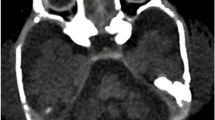

Patient summary

The proband is the first child to nonconsanguineous British Caucasian parents who was delivered at 40 weeks’ gestation after an uncomplicated pregnancy. Birth weight was 2.92 kg (9th percentile) and head circumference 32 cm (0.4th percentile). Physical examination was normal. At 16 h of age, she developed hypotonia and encephalopathy associated with hypoglycaemia, raised anion gap and metabolic acidosis with unrecordably high lactate. In intensive care, she remained unresponsive; acidotic and arterial lactate was 14 mmol/L. Creatine kinase was mildly elevated, and there was mild tubulopathy. Liver function tests were deranged, with abnormal coagulation profile. Workup for a treatable inborn error of metabolism and bacterial or viral pathogens was negative. Initial supportive evidence of mitochondrial dysfunction included high concentrations of proline and alanine in plasma, increased excretion of lactate and pyruvate in urine and reduction in homovanillic acid to 5-hydroxyindoleacetic acid ratio in cerebrospinal fluid (CSF) (Table 2). A muscle biopsy taken at day nine of life showed normal histology. Spectrophotometric assays of RCE activity (as described by Hargreaves et al. 2002) revealed mild reduction of cytochrome oxidase (complex IV) activity relative to citrate synthase (0.011, normal 0.014–0.034). Activities of complex I [nicotinamide adenine dinucleotide (NADH) ubiquinone reductase] and complexes II + III (succinate cytochrome c reductase) were normal (Table 2). Initial magnetic resonance imaging (MRI) of the brain revealed a small pons and dysplastic cerebellum with large bilateral cysts. A small lactate peak was resolved on MR spectroscopy (Fig. 1a, d and g).

A-I: a–c Axial T2-weighted magnetic resonance (MR) images of the brain taken at 5 days, 6 weeks and 7 months of age showing progressive loss of cerebral volume with delayed myelination and relative sparing of the basal ganglia. d–f Coronal T1-weighted MR images of the brain at 5 days, 6 weeks and 7 months of age demonstrating a butterfly pattern of cerebellar hypoplasia with bilateral cysts (+). There is progressive cerebellar volume loss that is most marked between 5 days and 6 weeks but is out of proportion to the degree of supratentorial brain atrophy. g–i Sagittal T1-weighted MR images of the brain at 5 days, 6 weeks and 7 months demonstrating marked progressive cerebral atrophy with progressive thinning of the pons (*), corpus callosum (**) and some degree of optic nerve atrophy (***), particularly between the first two scans

By day 3, the patient was extubated and blood biochemistry had normalised. At 10 days of age, she had a structurally normal eye examination, she was mildly hypotonic but alert, she fed orally and was discharged from hospital. At 4 weeks of age, she re-presented with status epilepticus requiring reintubation. She had frequent jerks, spasticity and fluctuating consciousness level. Her head circumference was 35 cm, now well below the 0.4th percentile for age. There were no biochemical abnormalities detected in blood and urine. Electroencephalogram (EEG) showed severely abnormal background with long periods of marked attenuation, interrupted by sharpened slow activities. Repeat MR imaging of the brain showed remarkable loss of cerebral and cerebellar volume with thinning of the corpus callosum and optic nerves. The basal ganglia remained relatively spared (Fig. 1b, e and h). Over the following 6 months she made no developmental progress, had poor visual attention, no social smiling and continued to have a severe combined seizure and movement disorder. After recovery from prolonged status epilepticus, repeat EEG showed bilateral frontocentral epileptiform discharges, with left-sided predominance. The background showed bilateral anterior more than posterior slowing, suggesting underlying cerebral dysfunction. Repeat brain MR imaging showed minimal worsening (Fig. 1c, f and i). At 12 months, she had near-continuous jerks interrupted by clinically correlated, electrographic seizures, disturbing sleep and required frequent sedation. She was almost entirely dependent on nasogastric feeds, with some pureed food. Auditory and flash visual evoked potentials were absent, with normal flash electroretinograms suggesting profound sensorineural hearing and visual loss. Ophthalmological examination revealed a structurally normal anterior segment, with pupils reacting sluggishly to light, gross pallor of mildly hypoplastic, cupped optic discs with normal intraocular pressure and gross thinning of the nerve fibre layer. This is consistent with secondary optic atrophy associated with loss of function of her anterior vision pathways.

Our case demonstrates the consistent neuroimaging finding of marked flattening or butterfly shape (Namavar et al. 2011b) of the cerebellum and cerebral volume loss, which appears to be progressive—in our patient, rapidly progressive—and is associated with concordant microcephaly. Cerebral and cerebellar atrophy is also observed in PCH3. In addition, these patients have corpus callosum thinning and early-onset optic atrophy (Rajab et al. 2003; Zelnik et al. 1996; Durmaz et al. 2009), which was observed for the first time in PCH6 in our patient (Table 3). Cerebellar cysts seen are a rare neuroradiological finding recently reported in a child with PCH2 due to TSEN54 mutations (Namavar et al. 2011b). The combination has also been described in association with bilateral frontoparietal polymicrogyria due to mutations in GPR56 (Chang et al. 2003; Piao et al. 2005). Cysts are also associated with congenital muscular dystrophies due to defects in dystroglycan glycosylation (Barkovich 1998; Clement et al. 2008). The specific neuroradiological changes seen in PCH6 are of interest, as they allow the potential for rapid recognition and genetic diagnosis, thus bypassing the need for muscle biopsy.